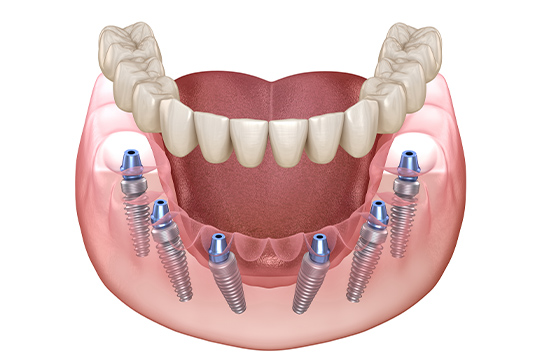

일상생활의 불편함을 줄이기 위해

임시치아를 제작하여 사용합니다.

저작과 심미 상태를 확인하며

최종 보철을 위한 준비를 진행합니다.